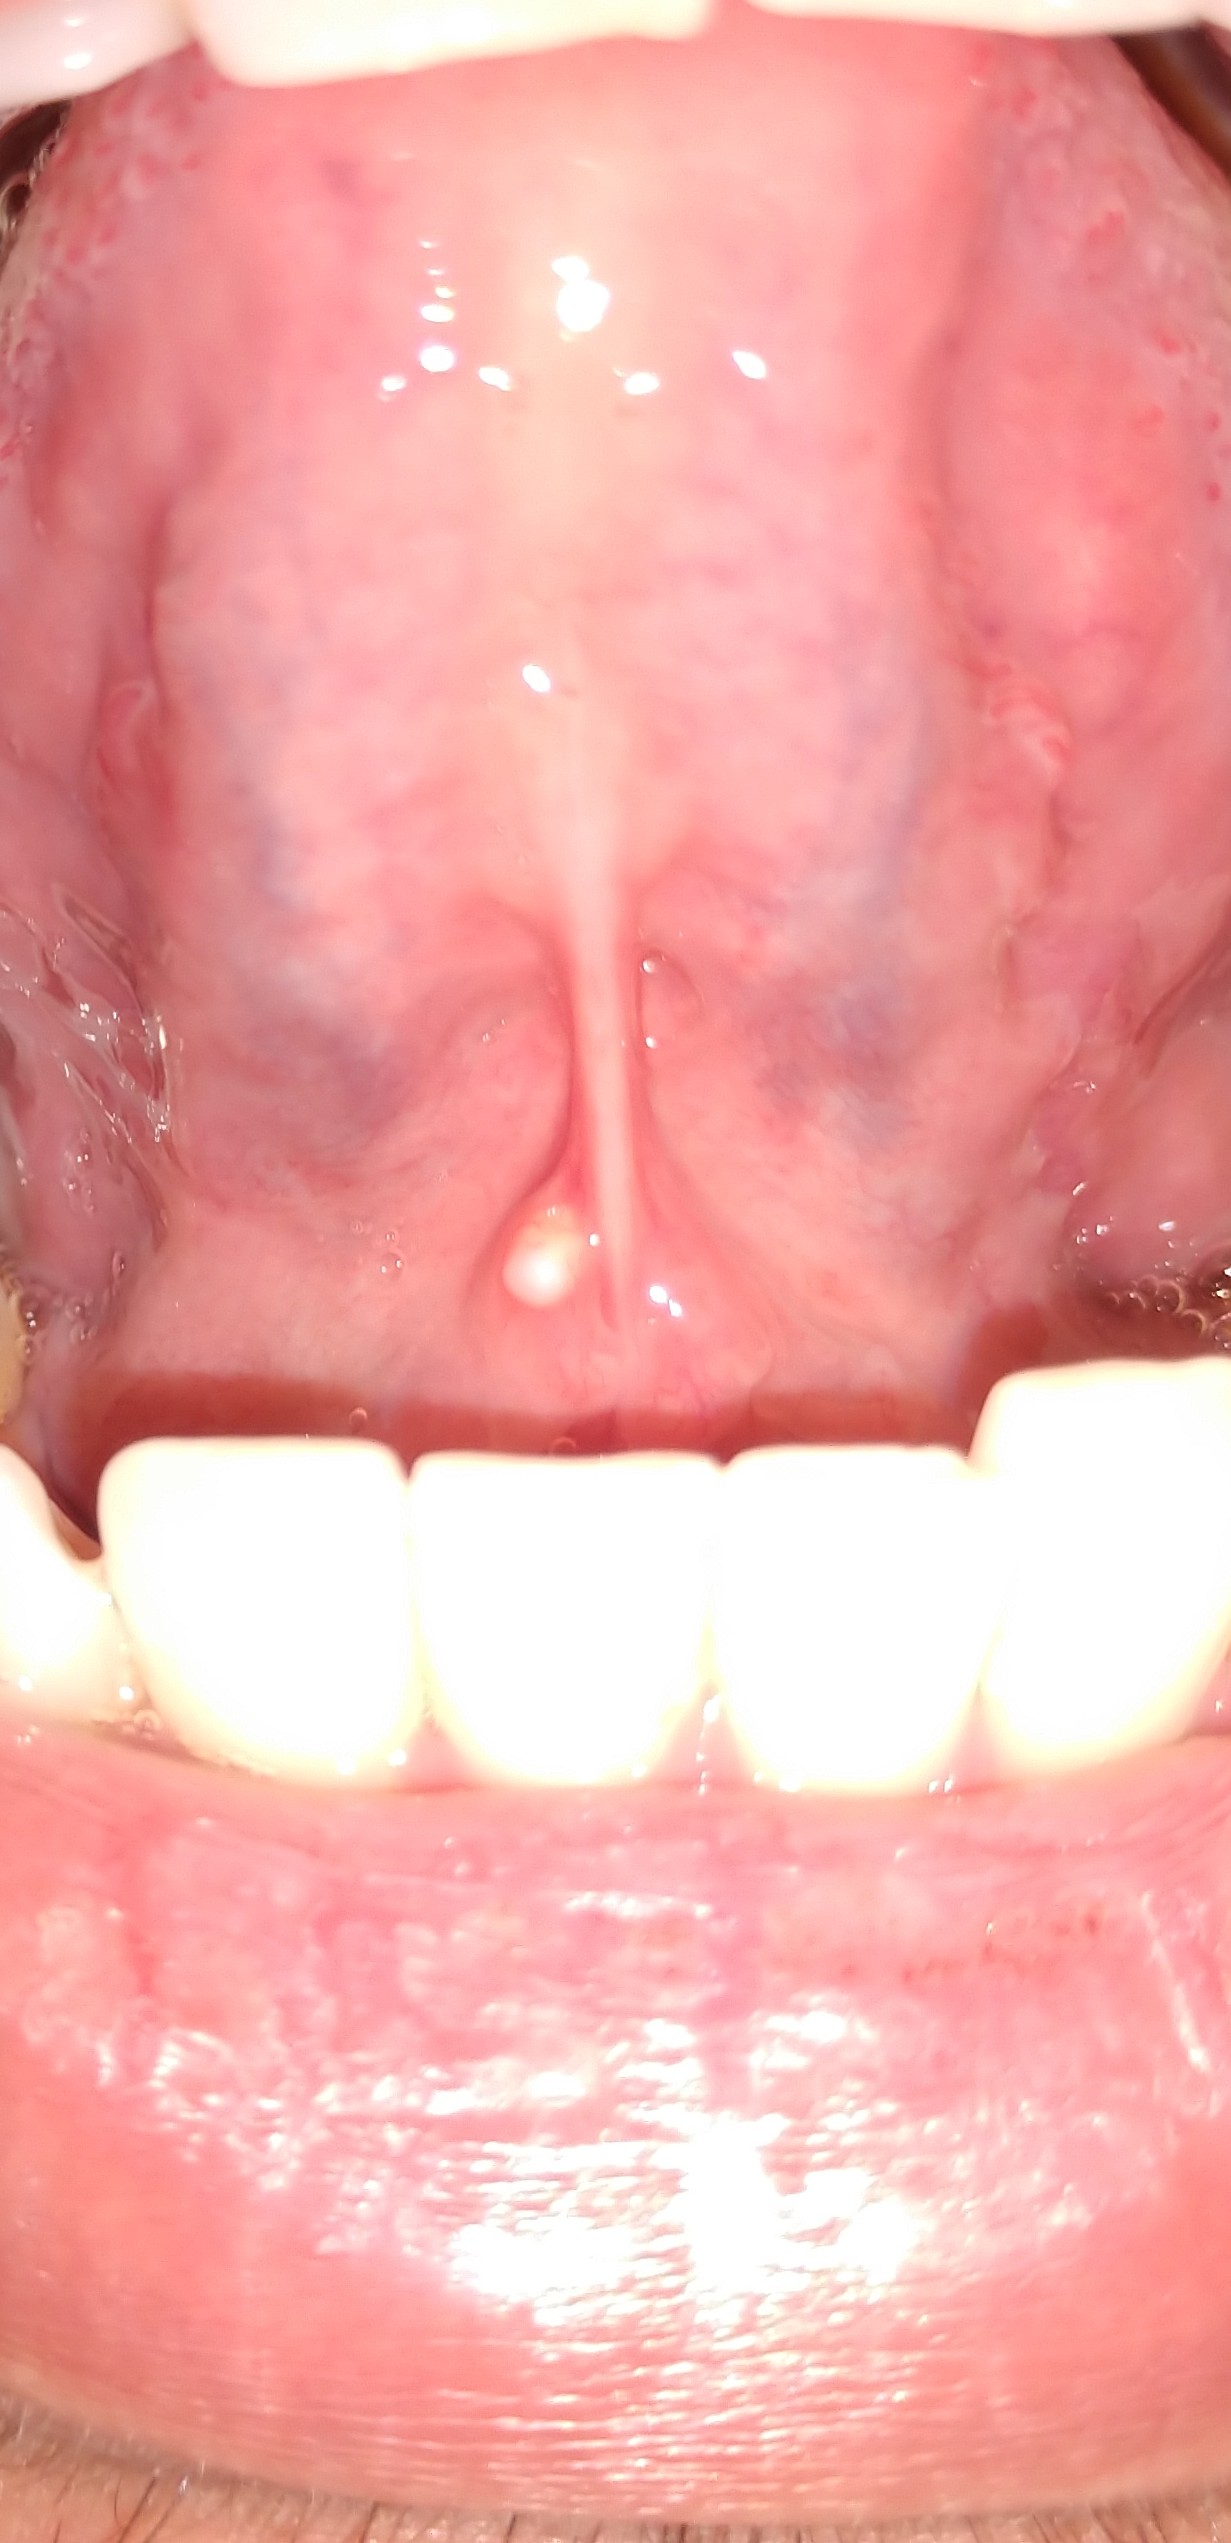

มีติ่งโผล่ออกมาไต้ลิ้นเป็นเพราะอะไรครับ

สวัสดีครับ ขออภัยที่รูปมันไม่สุภาพนะครับ มีไครเคยเป็นแบบนี้มั้งมั้ยครับสังเกตุเห็นมา2วันแล้ว

มันเกิดจากสาเหตุอะไรครับ ตอนนี้รู้สึกกังวลมากแต่ว่ายังไม่มีเวลาไปหาหมอ *ขอบคุณสำหรับคำตอบครับ